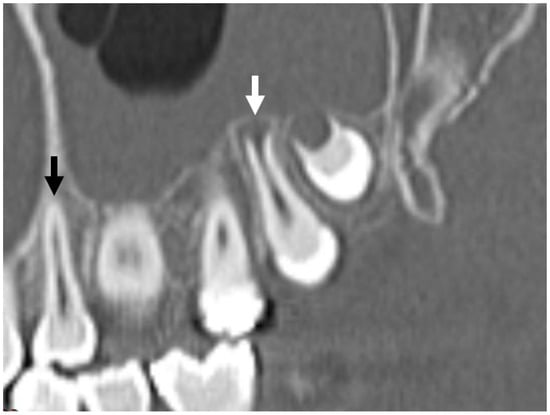

3.2. Dental Development

3.3. Radiologic Correlations of Embryological Development